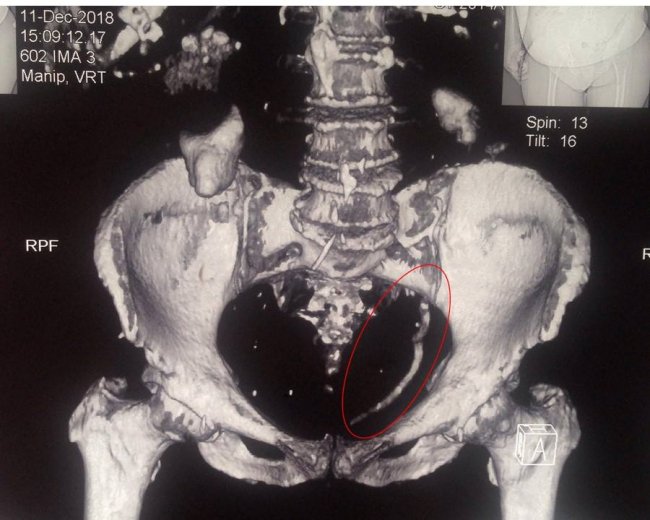

Ковельські лікарі провели контактне дроблення величезного каменю сечоводу розміром 15 см.

"Лікарями урологами Центру ендоурології ЦРЛ Ковельського МТМО успішно проведено контактне дроблення величезного каменю сечоводу розміром 15 см.", - повідомили медики.

Камінь спричинив повне блокування єдиної функціонуючої нирки, в зв’язку з чим у пацієнтки виникла важка гостра ниркова недостатність.